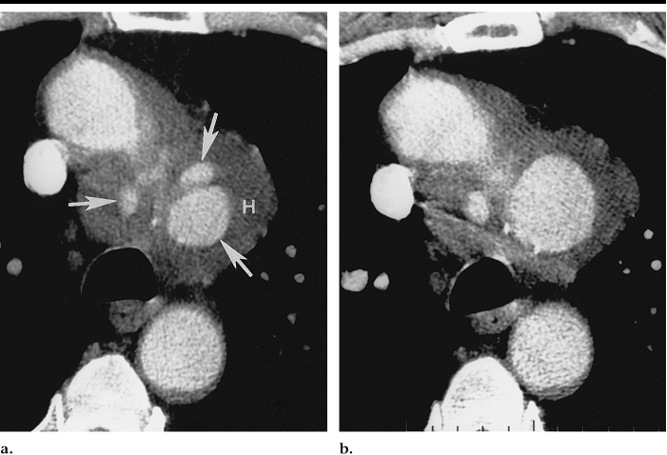

一线诊断手段:CT是PAU的一线诊断手段

大部分溃疡样主动脉病变保持不变随着时间的推移并且不会引起症状。大约三分之一的病变进展,通常导致伴轻度主动脉扩张,有时可能进展为囊状动脉瘤伴有主动脉扩张。对无症状的主动脉溃疡应行CT成像随访。